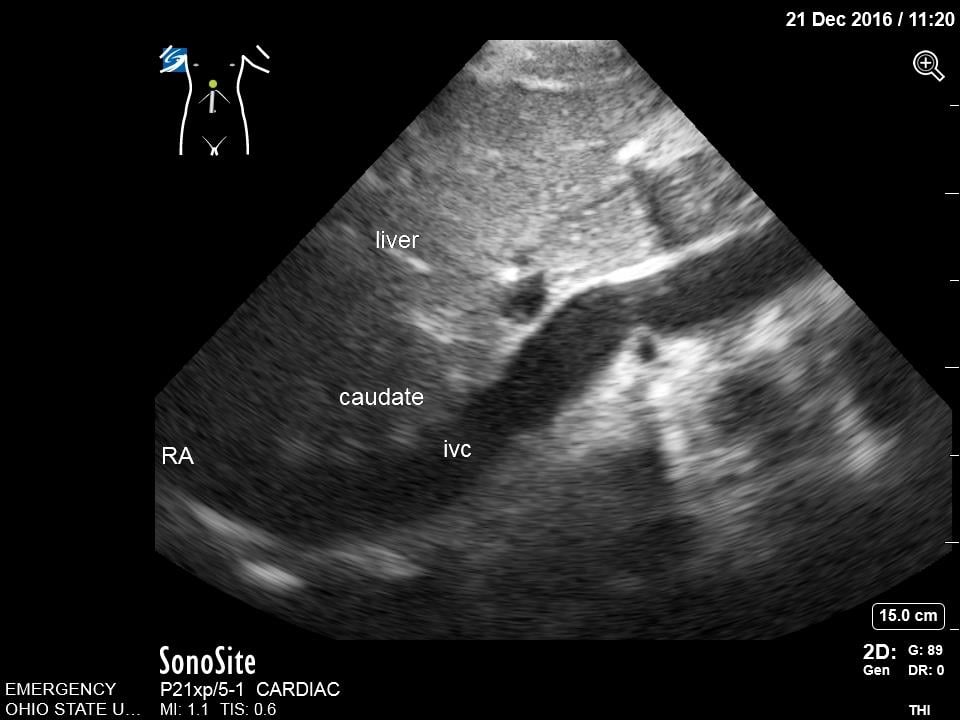

- Subxiphoid or Subcostal View: The liver is used as an acoustic window and is seen at the left of the screen and near field. The right ventricle being the most anterior is adjacent to the liver. The apex will be to the right of the screen. By fanning inferiorly, the inferior vena cava (IVC) is seen in short axis. Often the hepatic veins can be seen in the liver draining into the IVC.

- Subxiphoid or Subcostal View: The liver is used as an acoustic window and is seen at the left of the screen and near field. The right ventricle being the most anterior is adjacent to the liver. The apex will be to the right of the screen. By fanning inferiorly, the inferior vena cava (IVC) is seen in short axis. Often the hepatic veins can be seen in the liver draining into the IVC.

- Fan inferiorly to visualize the IVC in short axis. Rotate the transducer 180 degrees clockwise to visualize IVC in long axis. Note overall diameter and collapsibility with respirations approximately 2-3 cm distal from the right atria or just distal to the insertion of the hepatic vein.

- Figure 7. Subcostal Inferior Vena Cava in Long Axis. IVC = inferior vena cava. Caudate = caudate lobe of the liver. RA = right atrium